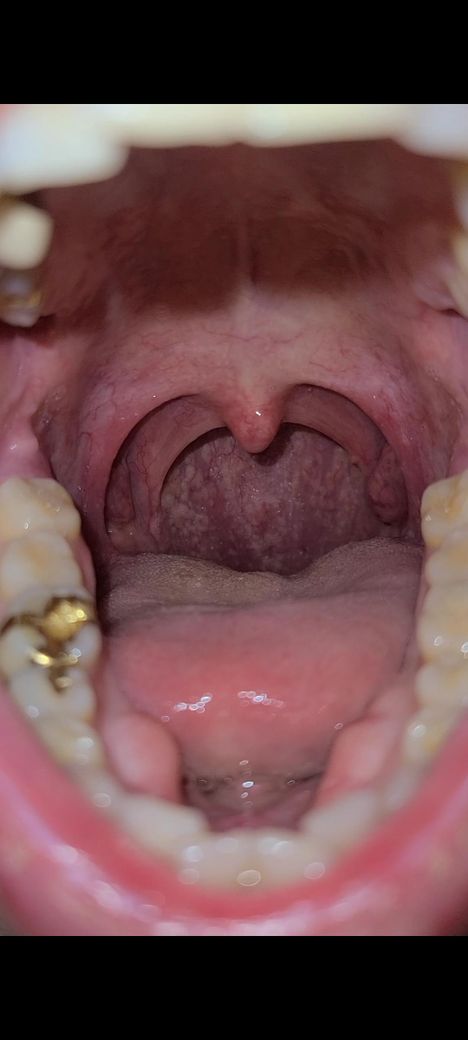

이거 편도가 부은건가요??제가 편도 비대칭인거 같은데

부은건지 모르겠지만 심한가요 상태 비대칭인데 궁금합니다 병원가야 할 정도인가요??아시는분

• 1번 째 사진

• 편도도 그렇고 몸이 완벽하게 대칭일 수는 없습니다. 사진을 통해서 보았을 때에 겉으로 보기에는 좌측의 편도가 오른쪽 보다 더 크게 보이긴 합니다만, 비정상적으로 크지 않으며 붓기가 있다고 판단할만한 소견이 따로 있어 보이지는 않습니다.